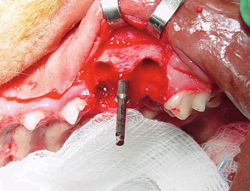

Canine dental implant

Figure 1B: Osteotomy being performed

Figure 1C: Implant being placed

Pictures shown are cases presented by Rocco Mele, DVM, of Tucson, Arizona, depicting a successful upper fourth premolar extraction, implant placement and bone graft performed on a dog at the same time and a second case of a canine extraction, implant and bone graft at the same time in a cat.